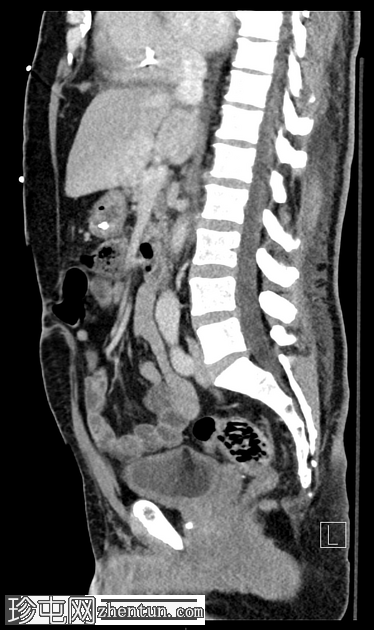

矢状C+门静脉期

小脐疝伴Richter疝,包含小肠前壁(肠系膜对侧部分),无梗阻或并发症。